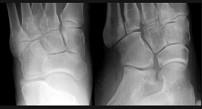

问题 女,25岁,扭伤后足中部痛,结合图像,最可能的诊断是 ( )

选项 A、中间楔状骨骨折 B、未见异常 C、外侧楔状骨骨折 D、足舟骨骨折 E、內侧楔状骨骨折

答案 E